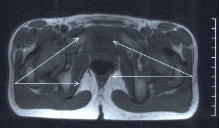

Innendrehgang

Innendrehgang bei Kindern

Ursache hierfür sind Drehungen im Bereich der Wachstumsfugen des Oberschenkelknochens. Der Unterschenkelknochen dreht den Fuß vom Kleinkindes- bis zum Jugendalter kontinuierlich um ca. 20 Grad nach außen. Werte zwischen 0 und 40 Grad Fußaußendrehung sind mit einer normalen Funktion vereinbar. Die Drehungen in den Wachstumsfugen aller Knochen sind trotz starker Unterschiede der Winkelwerte und der zeitlichen Abfolge präzise aufeinander abgestimmt .

Die Ursache des Einwärtsgehens liegt zwischen Fuß und Hüfte. Das Finden der Hauptursache bereitet im Einzellfall durchaus Kopfzerbrechen. Die oben geschilderte Entwicklung der Knochenform verläuft sehr unterschiedlich von Kind zu Kind.

Meistens werden Verzögerungen der Hüft-Drehung, Innendrehfehler der Unterschenkel (Sprunggelenke) und/oder Sichelfüße vorliegen.

MRT-Untersuchung zur Bestimmung der Drehachsen!